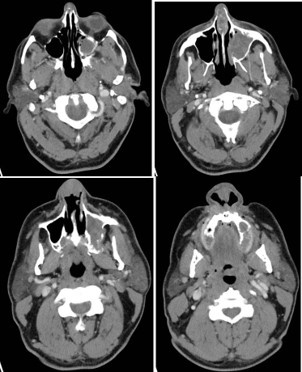

The new CT showed an ulcerated mass within the nasal cavity and a 1.4 cm septal perforation. Fluid and soft tissue were completely opacifying the left maxillary sinus. There was destruction of the nasal bone with the involvement of nasal skin, septal destruction with extension to the hard palate, and an extensive mass inside of the left maxillary sinus without any apparent orbital floor invasion (Figure 2). No cervical or distant metastases were appreciated at the time. The clinical Tumor, Nodal, and Metastasis (TNM) staging for the tumor was noted to be cT4N0M0. We recommended a left maxillectomy, left modified neck dissection with subtotal rhinectomy, and left chimeric scapular free flap for reconstruction.

The procedure began with a left Weber-Ferguson incision. The visible abnormal skin was marked out and removed. This involved 70% of the nasal dorsum extending from the rhinion to the cephalic aspect of the lower lateral cartilages and nasal ala. An intraoral left gingival labial sulcus incision was made extending to the midline of the soft palate and laterally to the gingivobuccal sulcus. The periosteum was elevated with a periosteal elevator, and a reciprocating saw was used to make bony cuts. These were performed through the right lateral nasal bone, junction part between the right maxilla and right nasal bone, and extending into the lower piriform aperture. Another bony cut was made horizontally between the nasal bone and frontal bone superiorly. This was extended to the left medial canthus to include the left orbital medial orbital wall rim and left orbital floor. Lastly, the saw was used along the left anterior maxilla with the intention of removing the maxillary sinus wall completely. Intraoperatively, the tumor was noted to extend into the left parapharyngeal space. Dissection was carried out, staying outside the palpable primary tumor while leaving a sleeve of healthy margin. The bony cuts were then used to cut through the hard palate on the left side and posteriorly separated from the soft palate. No bone cuts were made along the left nasal wall to ensure an en bloc resection. Soft tissue structures were then dissected freely. With the nasal cavity exposed, the saw was used to cut through the hole in the nasal septum. There were multiple defects present, including a skin defect around 6×4 cm, a mucosal defect of 3×4 cm, a left midface defect of 8×6 cm, and a hard palate defect of 6×4 cm. Margins were then carefully obtained and showed no residual tumor. A left modified neck dissection was then performed, and vessels were located for microvascular anastomosis.

A chimeric scapular free flap was chosen for reconstruction because it provides multiple bony components and skin for reconstruction. A 10×2.5 cm segment of the lateral border of the scapula and entire scapular tip was harvested along with the subscapular muscle. The skin paddle obtained was parascapular. The two components of the flap were noted to have two separate arterial origins but shared venous drainage. The flap was then placed into the defect of the face. The bony aspect of the flap was utilized to reconstruct the hard palate and maxillary defect with osteotomies (Figure 3). Proximal scapular bone was plated to the residual hard palate and distal portion to the anterior maxillary process. Two nasal trumpets were placed through bilateral nasal vestibules. The middle portion of the skin paddle was de-epithelialized and used to pack into the nasal cavity. Medpor supported the left orbital contents and was secured to the scapular tip. The scapular tip was affixed to the left zygoma and frontal bone with a reconstruction plate. Then, titanium mesh was used for the nasal bony defect, and the skin paddle’s distal end covered it entirely (Figure 4). The microvascular anastomosis was then performed, drains and nasogastric tube were placed, and incisions were closed. The patient was admitted to the intensive care unit, where hourly flap perfusion checks were performed using a Cook arterial monitoring probe. The patient followed an uncomplicated post-operative course, with discharge on the seventh day.